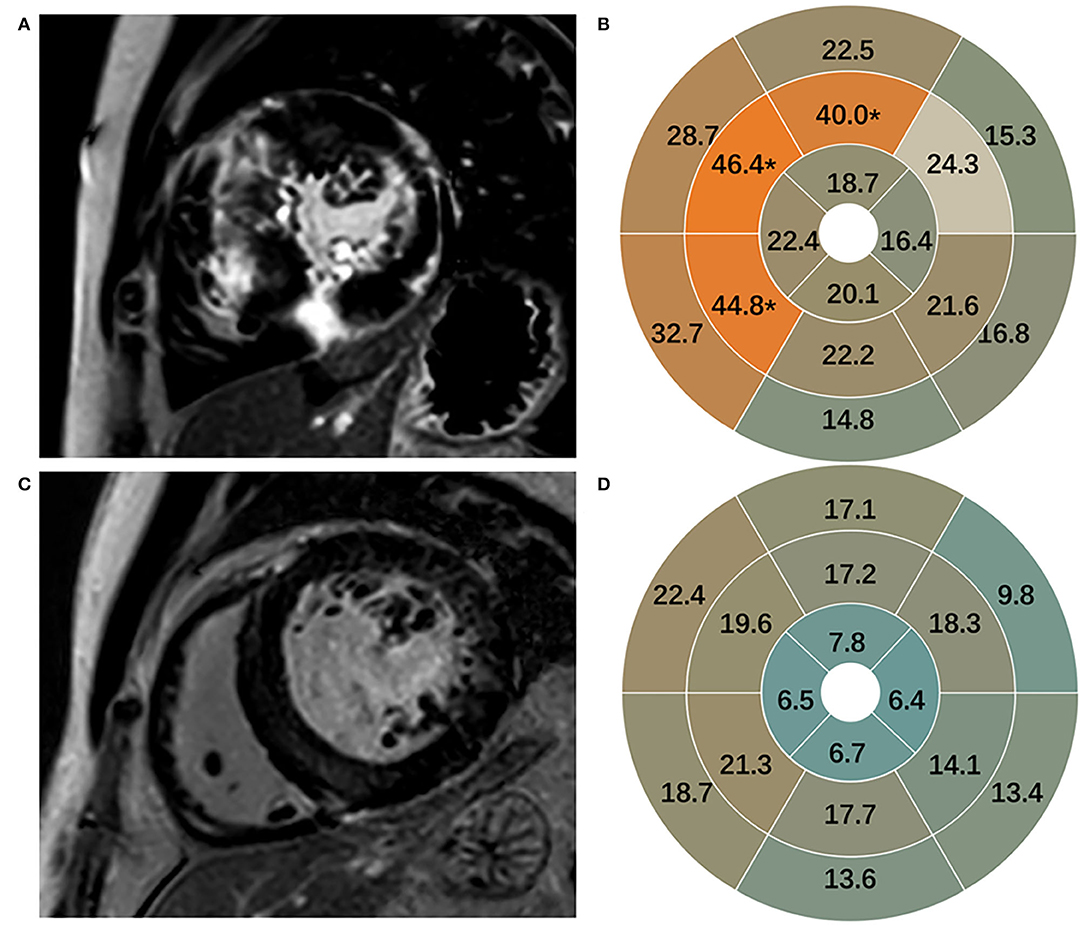

Late gadolinium enhancement was assessed in 170 participants and shown in Table 2. Healthy subjects presented no LGE. Patients with HCM in comparison to patients with HHD had higher values of LGE (total enhanced volume percentage) (P < 0.05). On segmental analysis, the differences in LGE values were predominantly localized around the interventricular septum (segments 7, 8, and 9; all P = 0.001), which corresponds to the mid-segment of the anterior, anteroseptal, and inferoseptal of IVS. It was also pronounced for mIVS (P < 0.001) (Figure 2), but there were no significant differences in other segments.

Figure 2. Representative images of LGE in HCM (A) and HHD (C). LGE in 16 segments in HCM (B) and HHD (D). LGE, late gadolinium enhancement; HCM, hypertrophic cardiomyopathy; HHD, hypertensive heart disease.